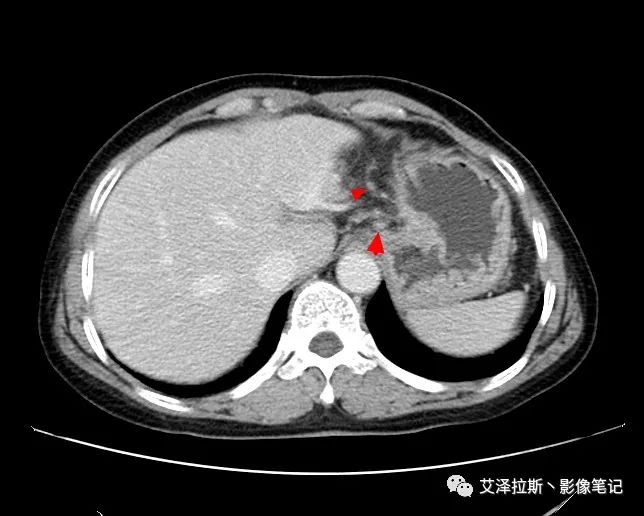

以下為累及的區(qū)域淋巴結(jié),共計15個區(qū)域:

【影像所見】 胃竇部狹窄,胃壁環(huán)形增厚,小彎側(cè)見一巨大潰瘍,周圍伴“環(huán)堤征”,漿膜面不完整,胃周脂肪見網(wǎng)格狀條索影,病灶與肝臟左葉、胰腺鉤突脂肪間隙消失,增強(qiáng)掃描病灶明顯強(qiáng)化。引流區(qū)內(nèi)約15個區(qū)域淋巴結(jié)受累。

【診斷意見】 胃竇部胃癌(T4N3期) 該病例腫塊突破漿膜層,與肝臟左葉、胰腺鉤突分界不清,脂肪界面消失,定為T4期; 受累及的淋巴結(jié)為15個區(qū)域,定為N3; 有無遠(yuǎn)處轉(zhuǎn)移尚不明確,所以M期暫時無法確定。